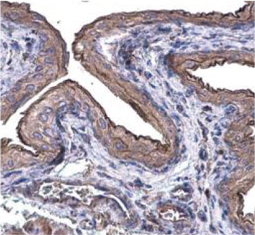

Cell markers are biochemical or genetic characteristics that distinguish and discriminate between different cell types. Although most are molecules expressed on the plasma membrane, cell markers are not limited to surface antigens and can include other components such as transcription factors. The unique composition and combination of cell markers allows researchers to accurately delineate the various cell types within a population. As the fields of regenerative medicine and molecular diagnostics continue to expand, the need to discover and describe novel cell-specific markers will become even more urgent.

GeneTex is proud to offer an outstanding selection of antibody reagents to facilitate your research, featuring antibodies against unique cell markers for detection of the various cell types highlighted below.